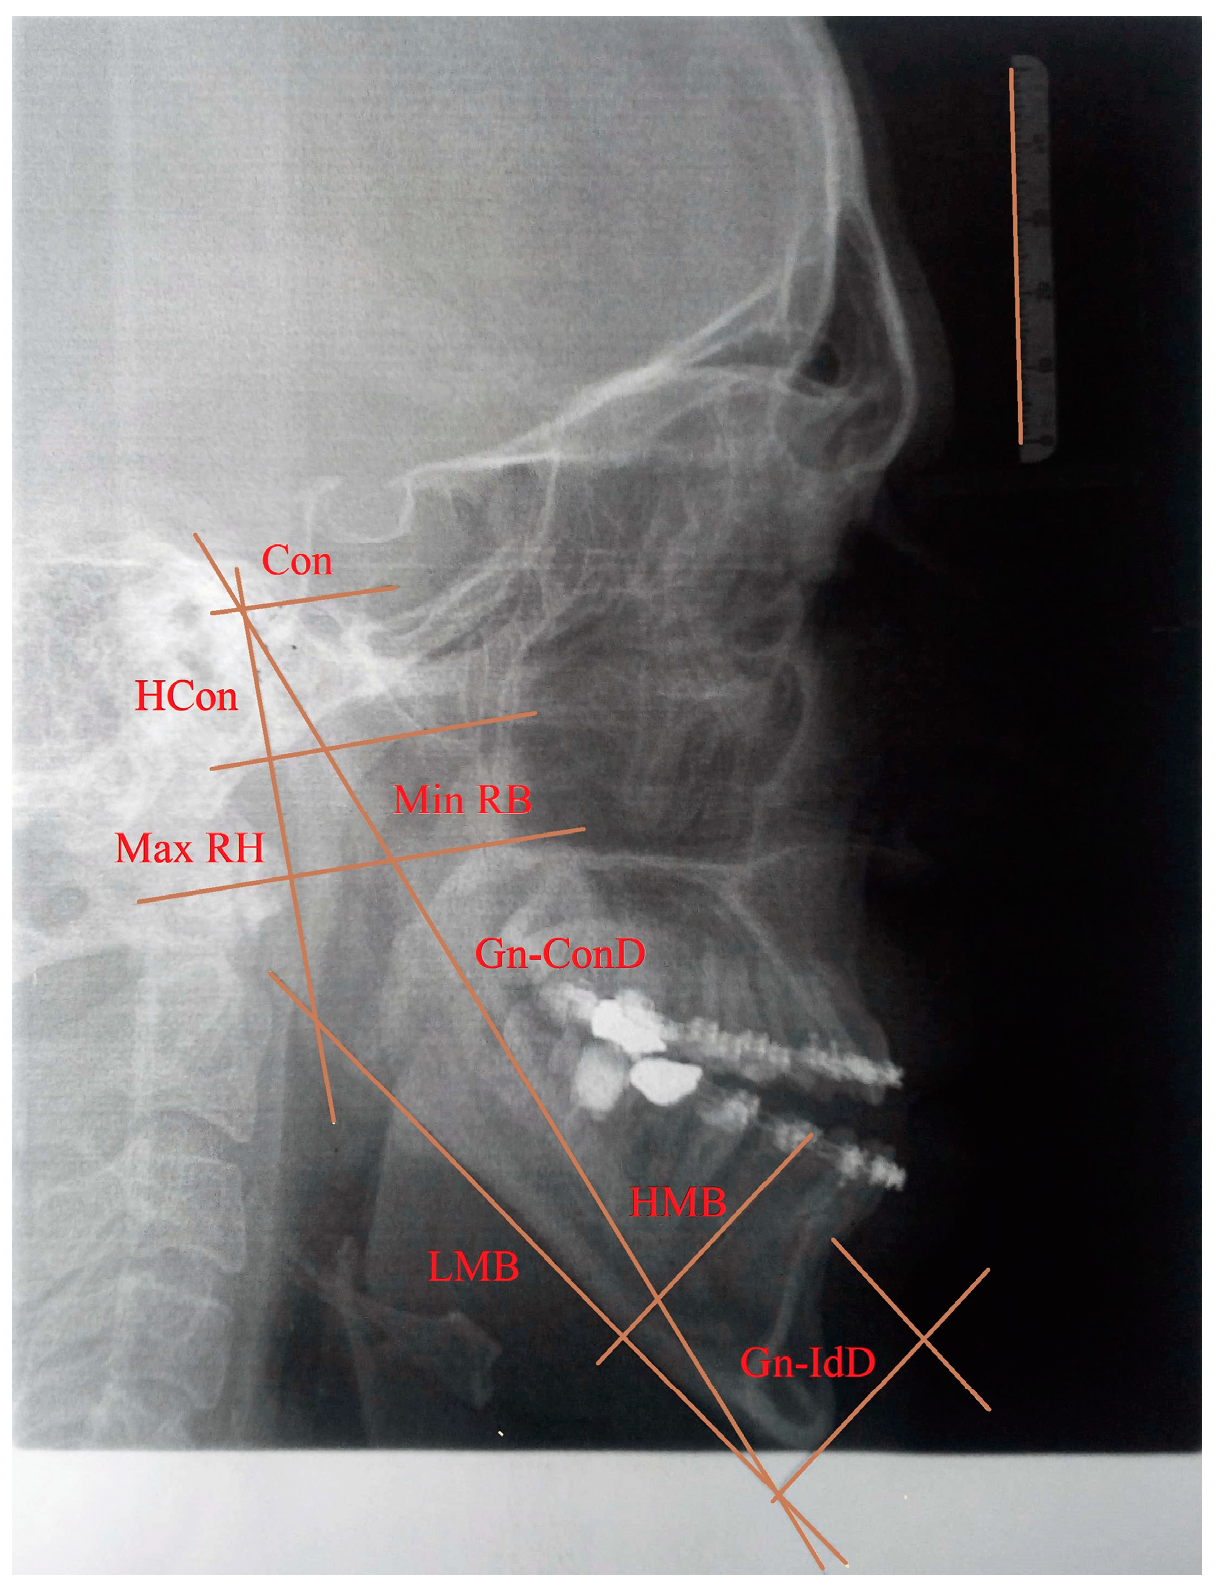

• Gnathion-interdental distance (Gn-IdD)—distance from the Gnathion to the alveolar septum between two incisors;

• Bigonial width (Go-GoD)—direct distance between right and left Gonion;

• Length of the mandibular body (LMB)—distance between Gonion and Gnathion;

• Gnathion-condylar distance (Gn-ConD)—distance between the Gnation and condylion (most prominent point on the mandibular condyle) anatomical points;

• Height of the mandibular body (HMB)—distance from the alveolar border to the mandibular base at the level of the Mental Foramen;

• Minimum ramus breadth (Min RB)—minimum breadth of the mandibular ramus measured perpendicular to the plane of the maximal height of the ramus;

• Maximum ramus height (Max RH)—distance between the highest point on the mandibular condyle and Gonion;

• Height of the condyle (Hcon)—distance between the condylion and the axis of the most inferior point of mandibular notch perpendicular to Max RH.

The input data for this analysis consisted of the measured values of morphometric parameters obtained from the 2D X-ray image and the 3D model of the patient. Due to the lack of both condylar processes, eight morphometric parameters (bigonial width, maximum ramus height, height of the condyle, length of the mandibular body, minimum ramus breadth, Gnathion–condylar distance, height of the mandibular body, and Gnathion–interdental distance) are used and presented in Figure 1. The measured morphometric parameters from the 2D image (length of the mandibular body, height of the mandibular body, height of the condyle, minimum ramus breadth, maximum ramus height, Gnathion–condylar distance, and Gnathion–interdental distance) were scaled according to the etalon size. The morphometric parameter bigonial width was measured from a 3D model of the patient using CATIA V5 R21, 3D CAD software. The measurements of the eight morphometric parameters are presented in Table 3. As a consequence of the excessive development of the mandible in the anterior direction, abnormal anatomical structures occur within the occlusion and the values of the morphometric parameters regarding the length of the mandibular body and Gnathion–condylar distance are high.

Figure 1. Morphometric parameters positioned on the X-ray image.